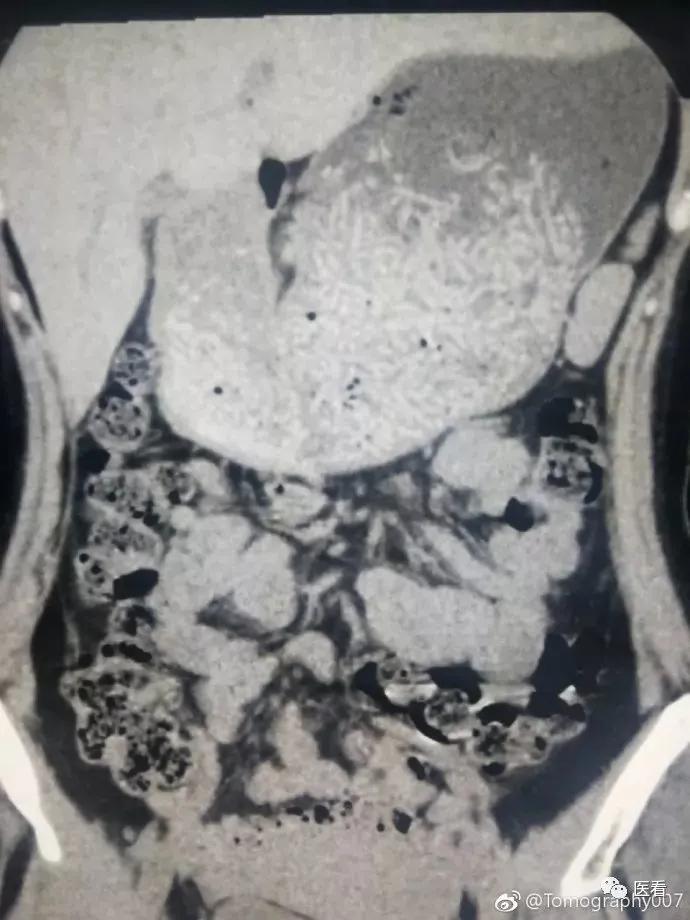

首先让我们来看一张片子

看看胃部,你能看出是什么吗?

这位病人来放射科检查,医生告知她空腹4小时,病人坚决不同意,各种骂街。

结果扫完就这个效果:能看出吃了好大一碗面,一个大胃占了半个肚子,里面塞满了面条。还能看出来病人根本没怎么嚼......

医生各种无奈,根本看不出来什么病。

这种经历可不是头一次了,还遇到过CT强化看胃部的,同样要求空腹,结果病人早上吃饭喝了点粥,胃里很多高密度影,没办法只能第二天重做。

放射科有的检查是必须要空腹的,如果吃了东西,扫出来的片子就会像上面那样,根本无法辨别。

这就是医生告诉你在检查前需要空腹的原因。